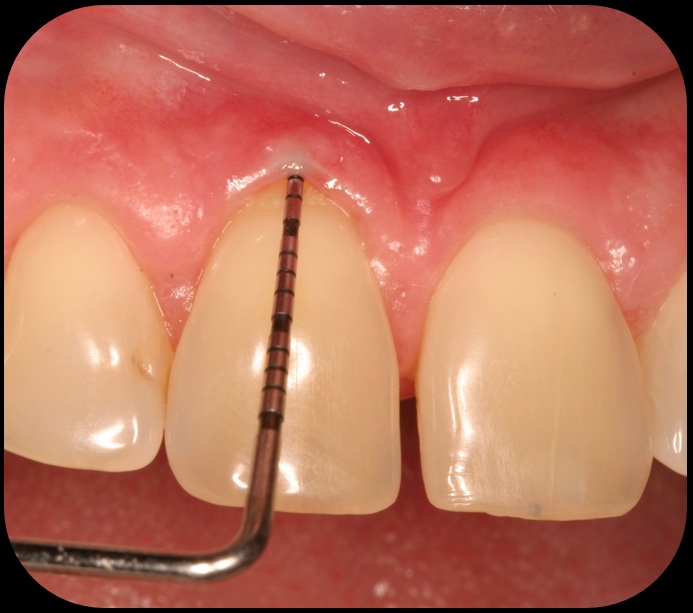

Evidence of clinical attachment gain.

Fig. 6